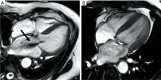

The natural history of mitral regurgitation (MR) results in significant morbidity and mortality. Innovations in non-invasive imaging have provided new insights into the pathophysiology and quantification of MR, in addition to early detection of left ventricular (LV) dysfunction and prognostic assessment in asymptomatic patients. Transthoracic (TTE) and transesophageal (TOE) echocardiography are the mainstay for diagnosis, assessment and serial surveillance. However, the advance from 2D to 3D imaging leads to improved assessment and characterization of mitral valve (MV) disease. Cardiovascular magnetic resonance (CMR) is increasingly used for MR quantitation and can provide an alternative imaging method if echocardiography is suboptimal or inconclusive. Other techniques such as exercise echocardiography, tissue Doppler imaging and speckle-tracking echocardiography can further offer complementary information on prognosis. This review summarises the current evidence for state-of-the-art cardiovascular imaging for the investigation of MR. Whilst advanced echocardiographic techniques are superior in the evaluation of complex MV anatomy, CMR appears the most accurate technique for the quantification of MR severity. Integration of multimodality imaging for the assessment of MR utilises the advantages of each imaging technique and offers the most comprehensive assessment of MR.